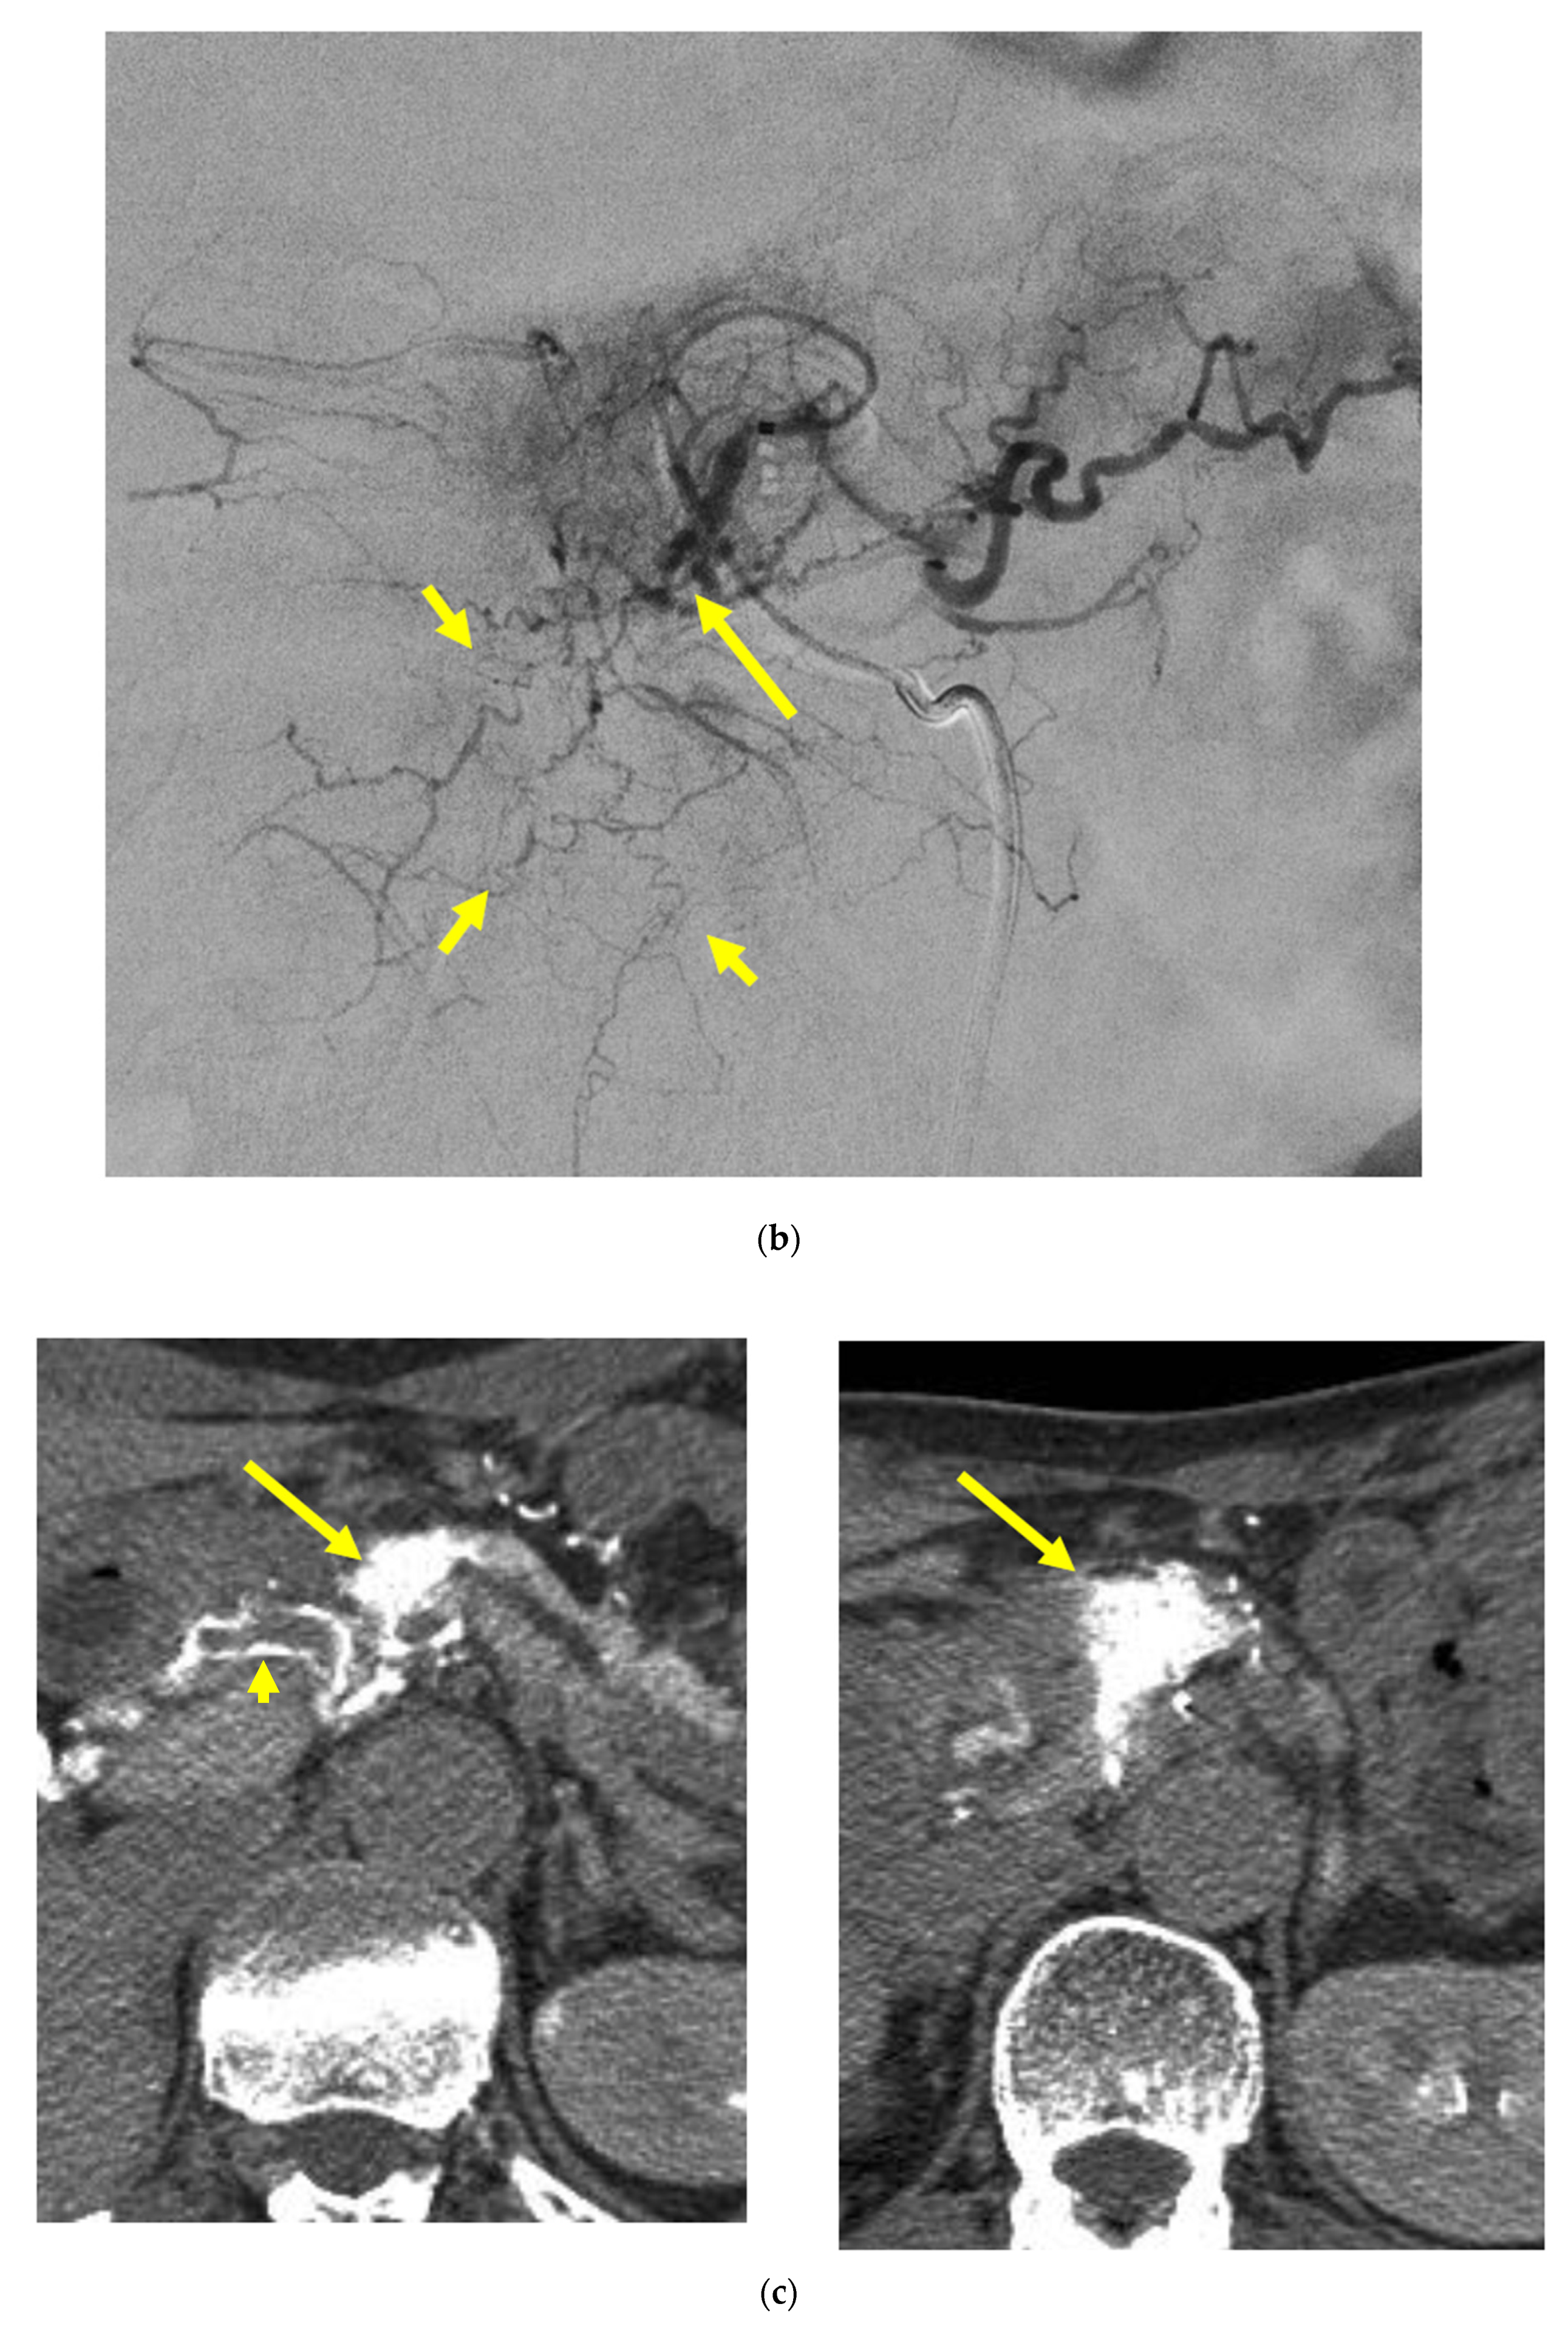

Identifying Supplying Arteries to Pancreatic Cancer

Method of Arterial Administration of Anticancer Agents